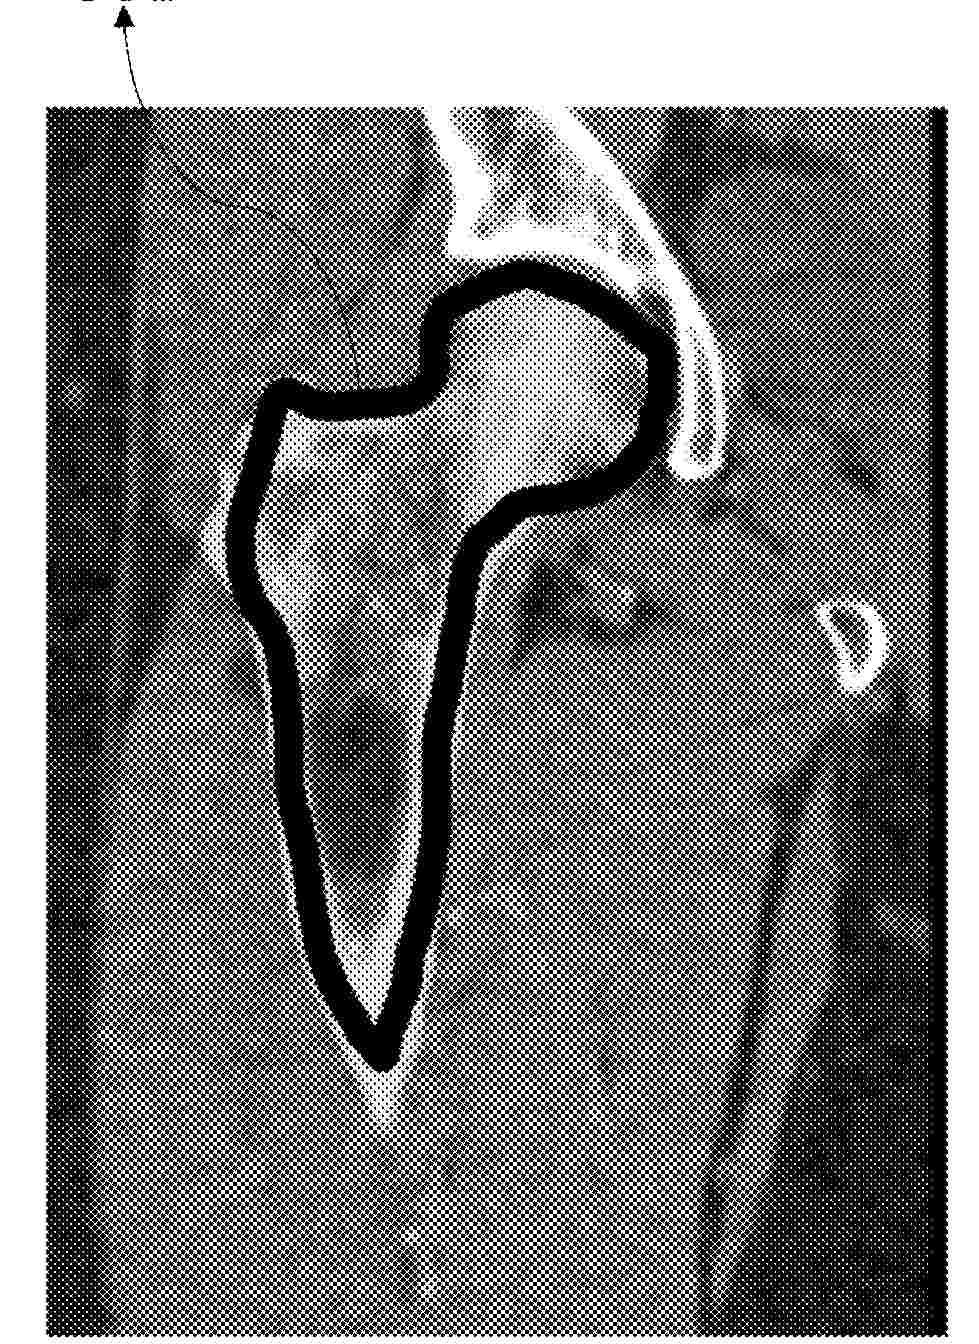

0000 A method for planning an orthopedic procedure including positioning a virtual implant component relative to a 3D volume of scan data of a patient using multiple 2D views of the scan data generated from the 3D volume at different view angles is disclosed. Positional information is developed using the generated 2D views with 3D positional information for the virtual implant component relative the 3D volume of scan data provided based on positional information developed relative to the 2D views.